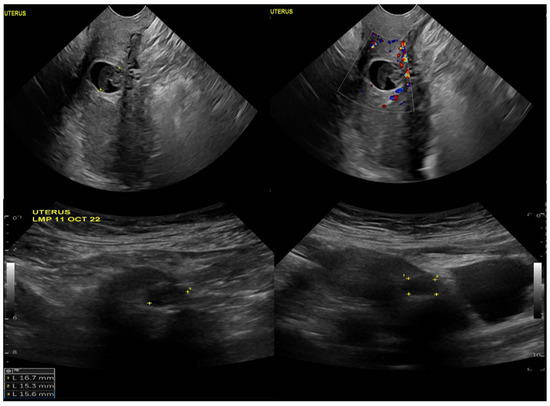

Upon physical examination, the patient was vitally stable with no active bleeding. A speculum examination showed a healthy-looking vulva and vagina, no bleeding, and a closed cervical os. The patient’s B-HCG level was 6878 mIU/mL, which increased to 9355 mIU/mL when repeated. A transvaginal ultrasound showed an average-sized uterus measuring 8 × 4 cm, a homogenous myometrium, and an endometrium measuring 4 mm with no definite endometrial gestational sac (Figure 1). The ultrasound also revealed a well-defined ectopic gestational sac showing a fetal pool with no definite pulsations in the anterior wall of the lower uterine segment at the assumed region of the previous scar.

Figure 1.

Ultrasound image of the uterus, demonstrating a well-defined ectopic gestational sac and showing a fetal pool with no definite pulsations in the anterior wall of the lower uterine segment at the assumed region of the previous scar.